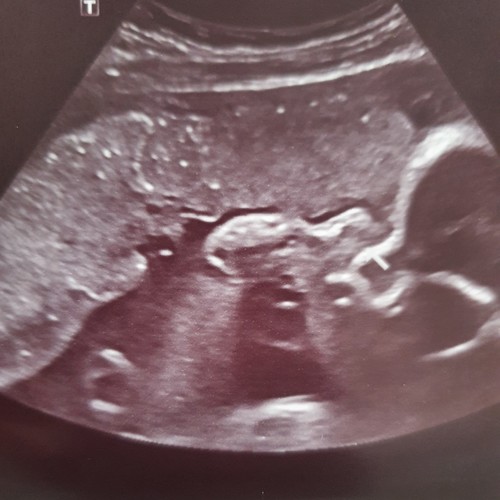

Gebeld en de vk zegt, ik was er niet bij en heb de foto's niet gezien maar als het iets opvallends was dan had je het gehoord en hadden ze het ook aan ons doorgespeeld, daar hebben wij goede contacten mee.(die school die de echo's maakt) ze zei dat het soms wel wat vertekend beeld kan zijn door bepaalde echo technieken o.i.d. Dus daar ga ik dan maar van uit. Ze beweegt in ieder geval flink en groeit goed... haha